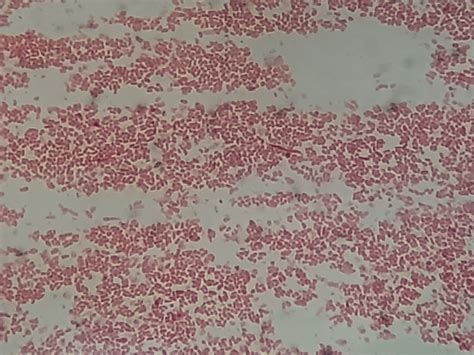

Understanding the intricacies of *Proteus Mirabilis Treatment* is crucial for healthcare professionals and patients alike. *Proteus Mirabilis* is a gram-negative bacterium that can cause a variety of infections, particularly in individuals with urinary tract issues or those who use catheters. Effective treatment requires a comprehensive approach that includes accurate diagnosis, appropriate antibiotic therapy, and preventive measures.

Proteus Mirabilis is a common cause of urinary tract infections (UTIs) and is known for its ability to form biofilms, which can make infections difficult to treat. This bacterium is often found in hospital settings and can lead to complications such as catheter-associated UTIs, wound infections, and respiratory infections.